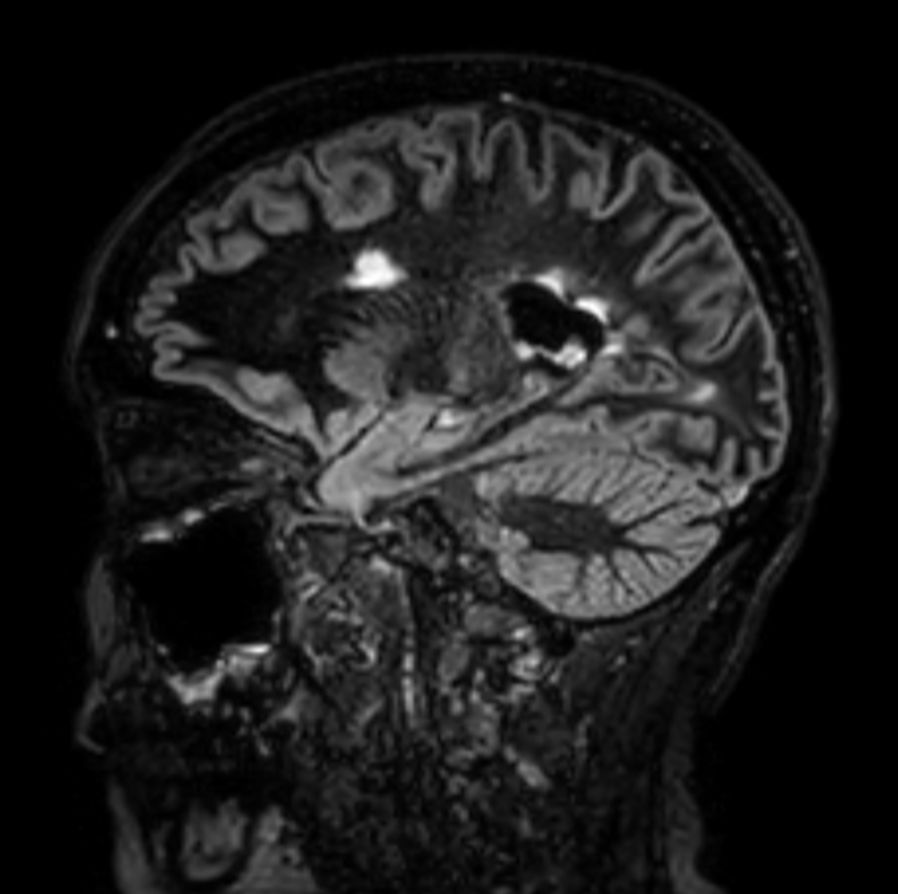

Multiple Sclerosis versus TIA

Standardized Multiple Slerosis MRI protocols typically require long scan times. Addition of Compressed SENSE enables faster exams, without compromise in image quality1. SWIp sequence has a high sensitivity to enhance contrast for deoxygenated (venous) blood or calcium deposits. This may help, when used in combination with other clinical information, in the diagnosis of various neurological pathologies. 3D (BrainVIEW) lets you acquire high resolution data in multiple directions in one scan. Isotropic voxel size enables reformats in any plane without loss of resolution.

3D T2w FLAIR BrainVIEW Compressed SENSE

3D T2w FLAIR BrainVIEW (reformat) Compressed SENSE